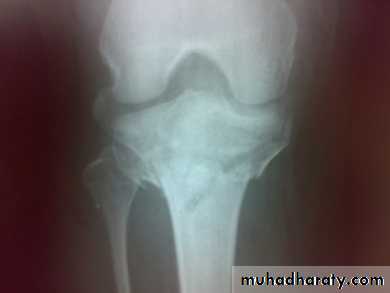

Tibial plateau fractures:Direct blow or fall from height may cause fracture of one tibial condyle or both.

Fracture lateral condyle is the commonest named as bumper fracture

caused by a force that abducts the tibia upon femur while the foot is fixed on ground.Patient usually is an adult, the knee joint is swollen, bruises, there is diffuse tenderness and doughy feel of haemarthrosis.

ligaments injuries must be excluded.

Imaging : X-ray

: anteroposterior, lateral & oblique views.

CT -Scan may used to detect amount of depression and comminuation.

Tibial plateau fracture